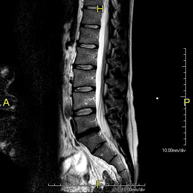

Prova diagnòstica no invasiva que consisteix en l'obtenció d'imatges d'alta definició anatòmica de la columna dorsal, mitjançant l'ús d'un camp electromagnètic i ones de ràdio (amb un emissor i un receptor). No utilitza radiació ionitzant. Indicacions: traumatisme, problemes degeneratius, hèrnies i tumors. - RM Columna Lumbar

Prova diagnòstica no invasiva que consisteix en l'obtenció d'imatges d'alta definició anatòmica de la columna lumbar i sacre mitjançant l'ús d'un camp electromagnètic i ones de ràdio (amb un emissor i un receptor). No utilitza radiació ionitzant. Indicacions: traumatismes, ciàtica, hèrnies discals, tumors i infeccions. - RM de Sacre-còccix